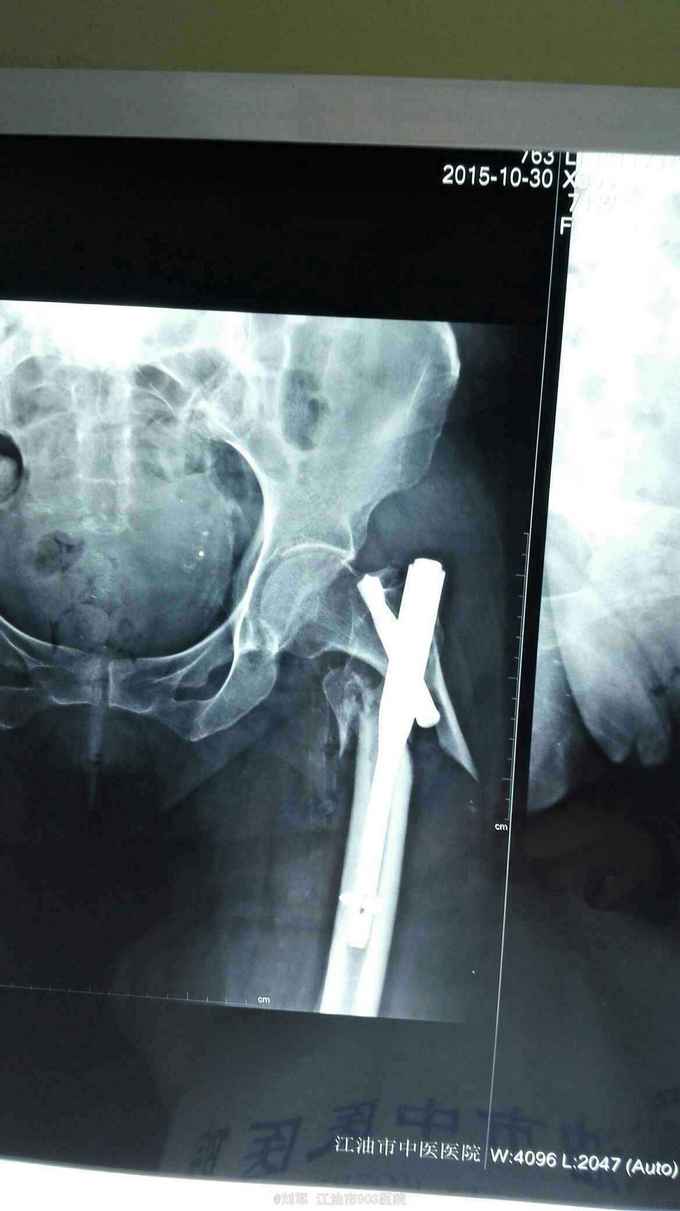

左侧股骨粗隆骨折术后骨折再移位20天。 患者74岁女性,20天前于外院行左股骨粗隆骨折PFNA内固定术。术后复查X片提示骨折再移位,内固定失败。来我院就诊。既往有糖尿病病史。入院时血糖控制可。贫血,低蛋白明显。HGB:68g/L。

左髋部肿胀,切口干燥,未拆线,无明显红肿、渗液。左髋关节活动障碍。

左股骨粗隆骨折术后再移位,2型糖尿病,